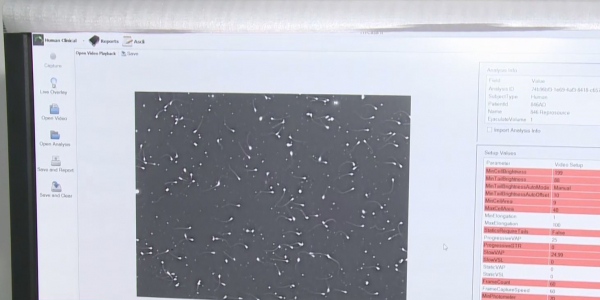

Долгожданное событие в отечественной репродуктологии.

- Казахстанская «девочка из пробирки» естественным путем зачала и родила ребенка